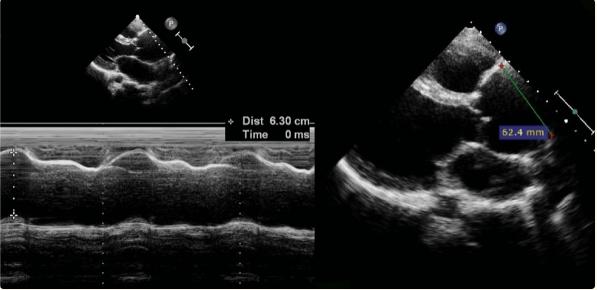

胸部X光显示心脏轮廓增大,提示左心室肥大。其他临床和实验室检查结果在正常范围内。经胸超声心动图显示膜周VSD、中度限制性分流(Qp/Qs=1.6)、AR和升主动脉瘤(图2)。经食道超声心动图证实了类似的发现(图3, 4)。

图2、升主动脉的超声心动图